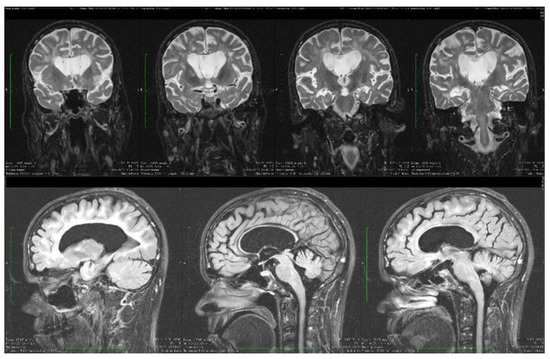

| Stoian et al. (our own case) | Case report | Male/4.5 months | Tonic seizures; later in evolution a left facial hemi spasm | 31 years | Reduced visual acuity (myopia), one and a half syndrome with left abduction nystagmus, left facial hemi spasms, divergent strabismus, flaccid tetra paresis, bilateral inconstant Babinski sign, gait instability, truncal ataxia, | Mild facial dysmorphism with thin upper lip and slightly spaced teeth | Social isolation, bradypsychia, bradylalia, echolalia, minimal linguistic baggage, behavioral stereotypes, MMSE17 points | Cryptorchidism | EEG: Poor unmodulated alpha activity, frontal intermittent theta activity; sharp waves and sharp peaks on the left central, parietal and temporal derivations | Brain CT: generalized sufferance pf white matter; cavum septum pellucidi, enlarged ventricular system, cerebral and cerebellar atrophy. Brain MRI performed before hospital admission: severe cerebral and cerebellar atrophy, vermis hypoplasia, supratentorial and infratentorial demyelinating lesions, cavum septum pellucidi, severe enlargement of the CSF spaces | Valproic acid, later replaced with levetiracetam and after a while with brivaracetam | The seizures disappeared under treatment being seizure-free since childhood; a left facial hemi spasm occurred lately |